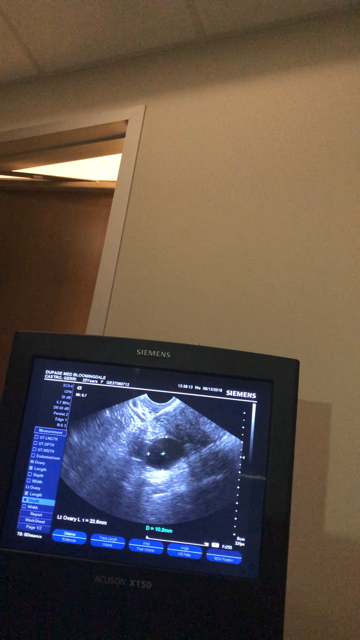

My first cycle I was on clomid 50mg days 5-9. I had 1 mature follicle and I ovulated by myself. But, my doctor said my progesterone was a little lower then he’d like it to be. So this month he decided to double my dose to 100mg of Clomid on days 3-7. I went in for my mid cycle u/s yesterday and my lining is good and thick and I have 2 mature follicles. One in each side. No trigger shot sense I’ve been ovulating myself. He hopes the higher dose of clomid will up my progesterone. I really want this to work. Fingers crossed!!!!!